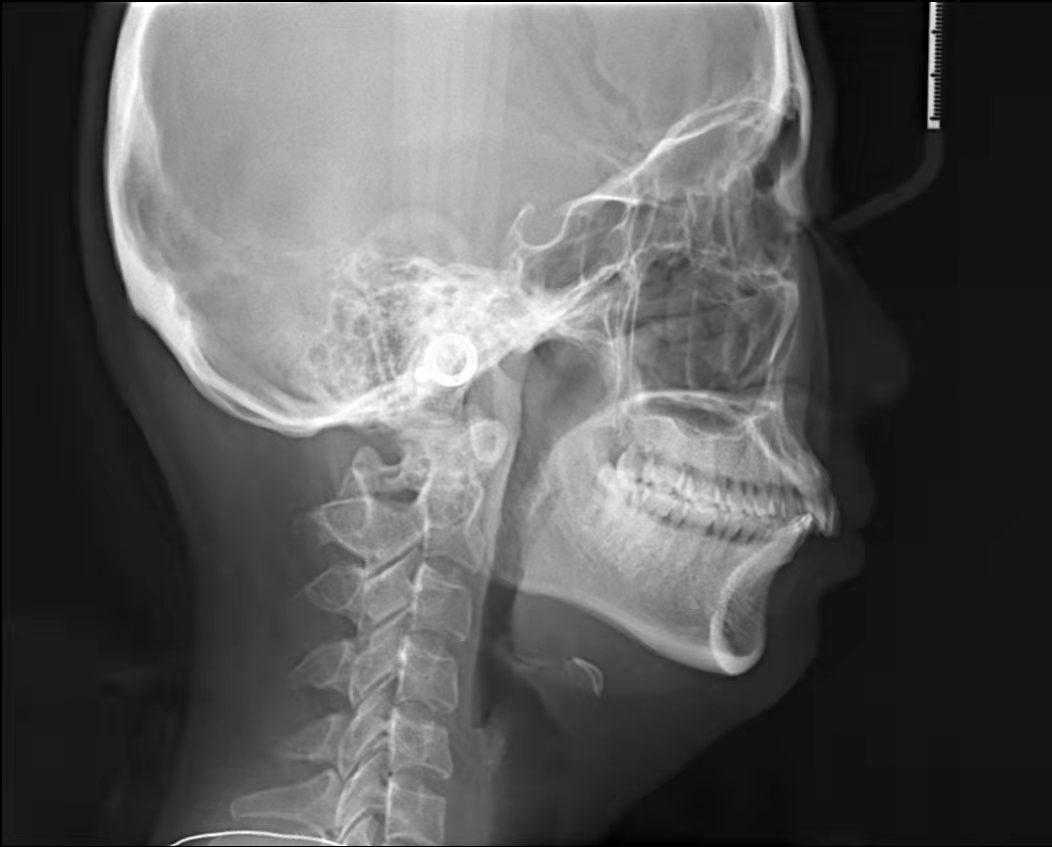

嘴凸不說下巴還后縮

沒有美美的側(cè)顏殺怎么拿下心動(dòng)男孩呢?。?/span>

咱不提倡整容!但咱天生的下巴要給他使喚出來吧!所以很多妹紙沒有下巴有可能不是天生的呢!

4、齙牙造成面部變形。臉型在人體美中占有重要的位置,臉型的美麗與諧調(diào),是由的牙列來維持的。齙牙咬合受影響,導(dǎo)致面部不協(xié)調(diào),從而加速面部衰竭,由于臉部的骨骼結(jié)構(gòu)也會(huì)影響皺紋形成,齙牙嘴型往前凸,恰好在法令紋位置形成凹陷,法令紋自然會(huì)加深。而且牙槽骨或整個(gè)頜骨因缺乏正常咀嚼氣力的刺激,將會(huì)逐漸蛻變、萎縮,造成下巴的長(zhǎng)度變短,面頰部和四面肌肉松弛,甚至?xí)斐擅娌孔冃巍?/span>